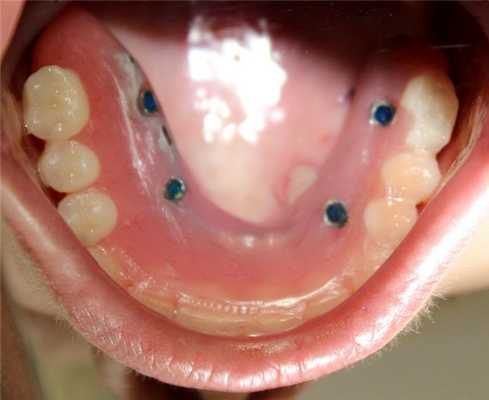

- Примерка и установка мультиюнитов и ушивание (фото 13)

- По окнчании операции был фиксирован армированный адаптационный протез - фото через 3 суток после операции (фото 16, 17)

Через 6 месяцев после операции первичные адаптационные протезы были заменены на новые адаптационные протезы с армированием (фото 18, 19, 20, 21, 22). Фотографии выполнены через 8 месцев после функционирования второго адаптационного протеза. На снимках видно достаточное количество прикрепленной слизистой, которое удалось создать благодаря правильному позициониравнию имплантатов и естественному заживлению после удаления (фото 23, 24).